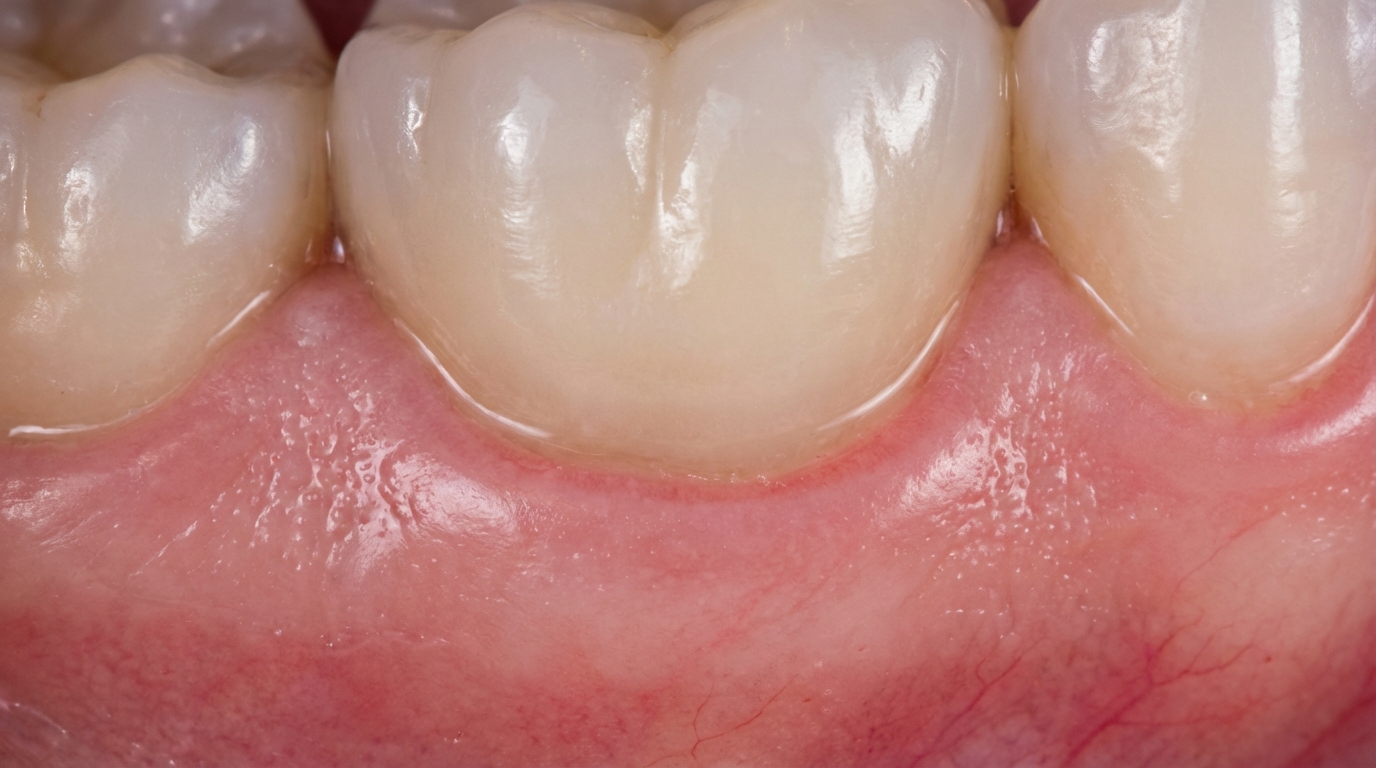

How does it interact with gum tissue?

Research into the dental industry shows that zirconia promotes healthy gingival attachment and resists plaque accumulation. Its smooth surface prevents bacteria from adhering, which significantly reduces the risk of gum disease around the crown. Patients often notice that their gums remain pink and healthy rather than developing a dark, irritated line.

Here is the deal:

- Bio-inert: Does not react with saliva or acidic foods.

- Plaque Resistance: Smoother than natural enamel to keep bacteria away.

- Soft Tissue Friendly: Encourages the “creeping” of gums for a natural look.

- Galvanic Protection: No “metal taste” or electrical sensations in the mouth.

The material’s interaction with soft tissue ensures that the restoration remains aesthetically pleasing and biologically sound for the long term.

- No Gray Line: Since there is no metal, the gum line stays bright and natural.